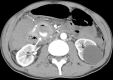

Presentation of case: A 62-year-old man with a two-day history of epigastric pain was admitted at emergency department. CT showed a retroperitoneal haematoma due to a 1.5cm posterior inferior PDA ruptured aneurysm. Angiography had been conducted immediately: both inflow and outflow of the aneurysm were embolized. Another CT scan had been conducted, which revealed residual flow inside the aneurysm sac fed by small collateral vessels. Sub-selective catheterization was repeated and definitive haemostasis was obtained by embolizing the collateral vessels. Postoperative course was uneventful. CT scan follow-up at 36 months showed no abnormalities.